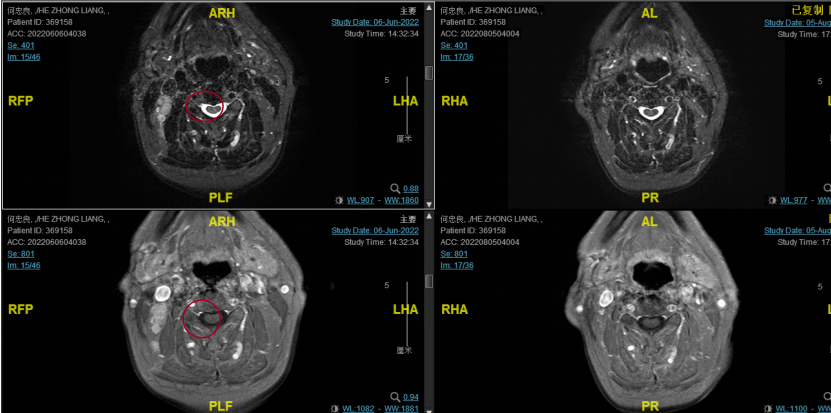

2022-08-05(放疗近结束)复查MR,疗效评价:CR。鼻咽部肿物及咽后转移淋巴结颈部转移淋巴结均达到CR。